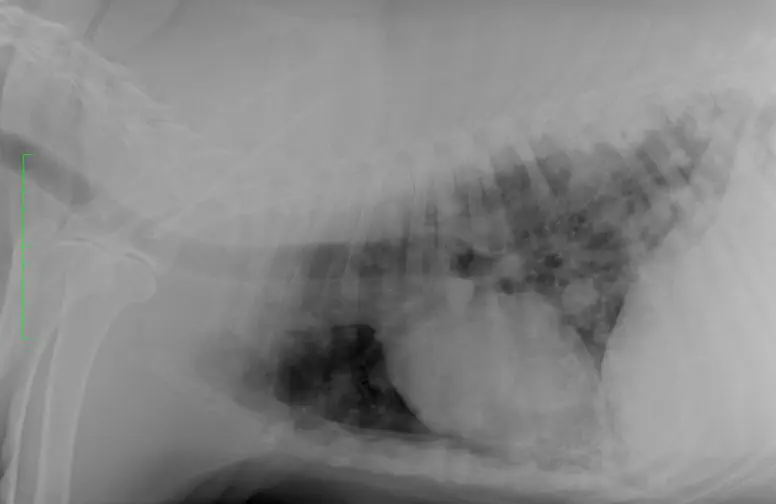

胸部レントゲン検査

肺野の異常の有無、気管および気管支の評価、胸郭や横隔膜の評価などを行います。

肺腫瘍(血管肉腫)の犬